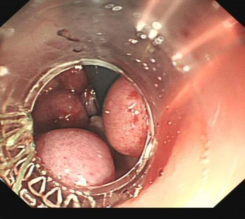

食管胃底静脉曲张内镜下套扎、组织胶治疗

肝硬化食管和胃底静脉曲张破裂出血的内镜下组织胶注射和套扎序惯治疗